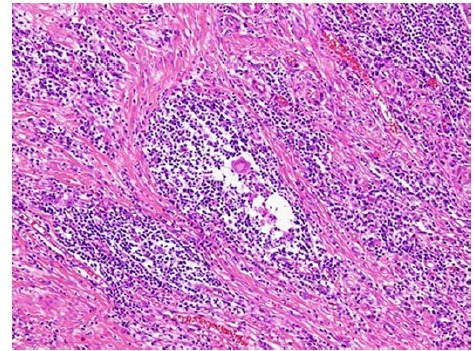

标本经福尔马林固定后每 3-5mm 组织切片。组织学检查显示明显的炎性淋巴细胞、浆细胞浸润和黏膜下层和固有肌层之间纤维化(图 6 和图 7)。解剖瘢痕处及淋巴结均没有发现癌细胞。

图 6 炎性淋巴细胞、浆细胞浸润,黏膜下层和固有肌层之间纤维化明显,表面覆盖退化的粘膜层。

图 7 微观显示炎性细胞浸润,无肿瘤细胞